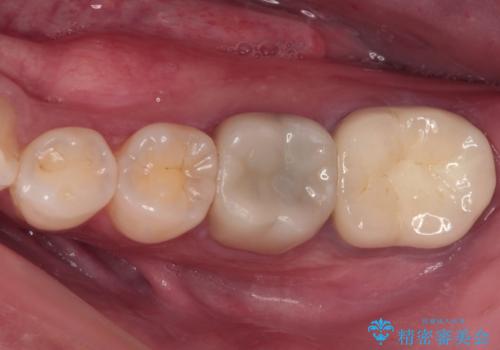

奥歯がズキズキと痛む 奥歯の虫歯治療